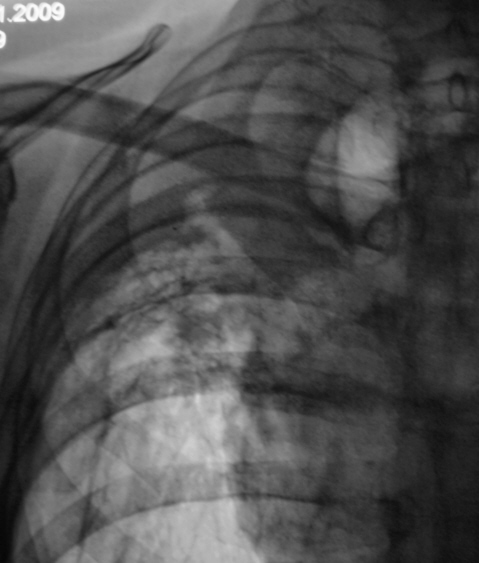

И правильно засомневались, очень на центральный рак похоже. Кстати рак на фоне туберкулеза совсем не редкость, как полагали раньше. А что в заднем отрезке 6 ребра справа - деструкция?,

Об этом и думали после прошлого исследования, но ЦВК, есть ЦВК. Сейчас размещу сегодняшние снимки, но я не так "круто", как Вы - "рак". Просто констатировали "культю", и пускай "поставившие" расхлебывают.

но узел то есть, не только культя...

Конечно же такие случаи надо сразу дообследовать (бронхоскопия, КТ), а не "наблюдать" раз в год... Ребро на новых снимках вроде целое, на предыдущих наверное наслоилась  плевра. Хотелось бы еще разобраться, что с восходящей аортой происходит.

А может, то не "чистая аорта", а аорта + конгломерат? Поищу боковой.

Скорее всего, но: подрастает ли опухоль к аорте и нет ли аневризмы?